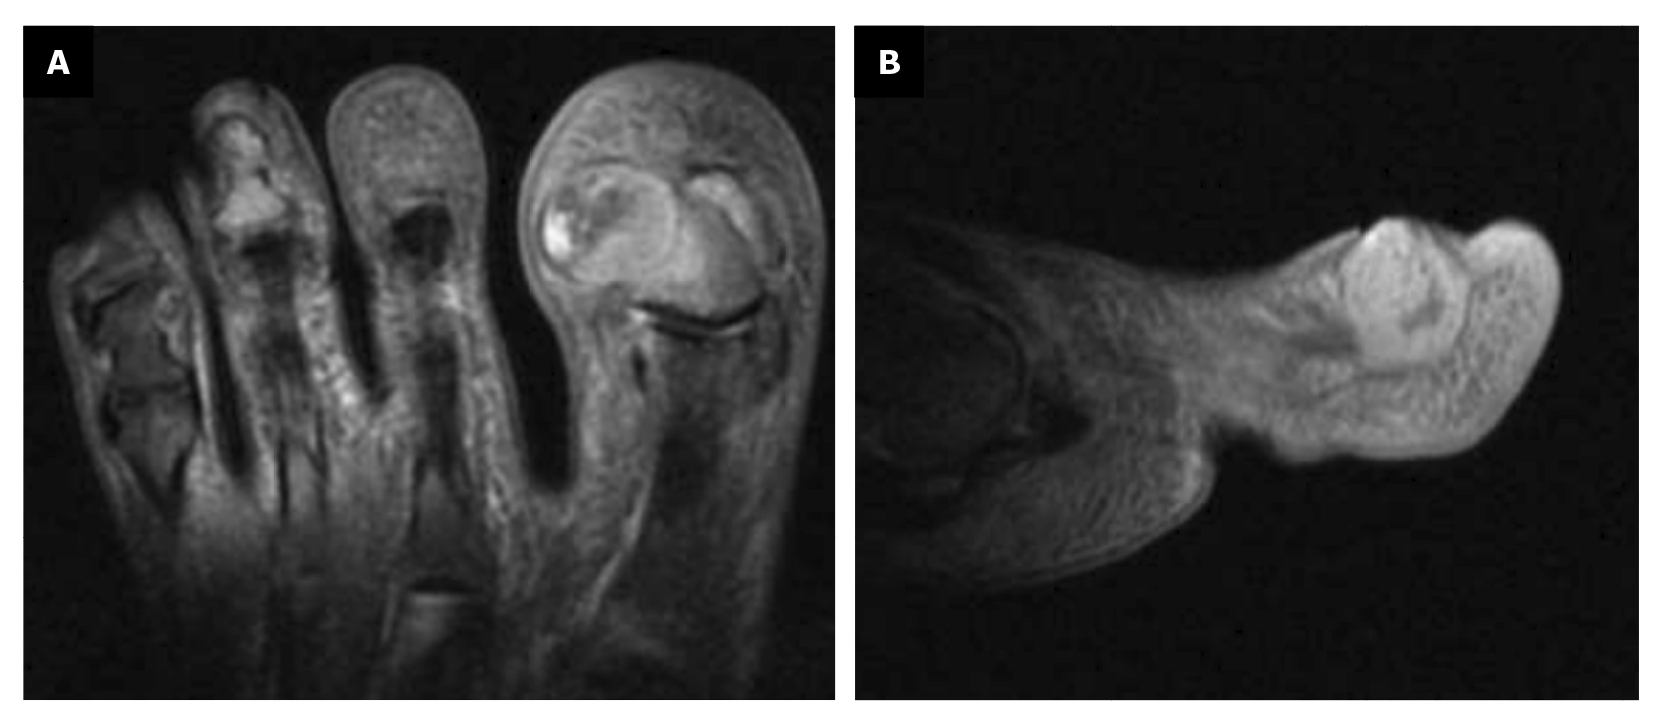

Within 3 weeks after the third intervention, the patient reported recurrence of the lesion and painful symptoms (Figure 7). The patient decided to attend the traumatology department (February 2023) where an MRI (T2FS and DPFATSAT) was requested. It showed an occupying mass in the lateral third of the first toe with well-defined borders and bone involvement (Figure 8) with the following report: “At the level of the distal phalanx of the 1st toe in the nail region, there appears to be a solution of skin continuity with a heterogeneous, a dense 15 mm x 14 mm collection in the lateral region of the parapharyngeal soft tissues, remodeling the bone and coming into contact with the flexor tendon, which could be consistent with a postoperative abscess/phlegmonous collection. Some bone edema in the distal phalanx is suspected, without completely ruling out incipient osteomyelitis. To be correlated with medical history and surgical protocol performed.”

Figure 8. Space ocuping mass with bone involvement. A: transverse plane; B: saggital plane.

The Traumatology Service referred the patient to us, and she attended our center on February 27th, 2023. On March 1st, 2023, we decided to perform surgery with excisional biopsy of the lesion, with 5 mm safety margins around its contour. The lesion was completely removed, and given the bone involvement of the lesion, partial resection of the lateral border of the distal phalanx of the 1st toe was performed. Both samples (soft tissue and bone) were sent to pathology separately. Finally, the incision was closed with approximation sutures (Nylon 4/0) in the proximal and distal areas; since the primary defect was too large, the central area of the incision was left open to close by secondary intention with the use of hydrofiber (Figure 9).

The histopathological study of the samples described for the first sample: “Skin with a hyperkeratotic tumor composed of squamous cells with discrete atypia forming an expansive border with some cords and nests infiltrating the dermis. Lateral surgical margins free and deep margin affected. DIAGNOSIS: Well-differentiated infiltrating squamous cell carcinoma affecting the deep margin,” and for the second sample: “Bone tissue with bone trabeculae and adipose tissue between them without alterations. Focally, two small nests of well-differentiated squamous cell carcinoma are observed. DIAGNOSIS: Bone tissue with focal infiltration by well-differentiated squamous cell carcinoma.”

5 days postoperatively, the patient’s first dressing change was performed, which showed a good appearance and no local infection. The patient was explained the result of pathology and referred to the oncology service of her hospital, and from there to the dermatology and plastic surgery service where digital amputation was performed (Figure 10). Subsequent follow-up was conducted by the Oncology service for the next 6 months. After different tests, it was determined that no other treatment was needed. Figure 11 shows the timeline of the clinical case.